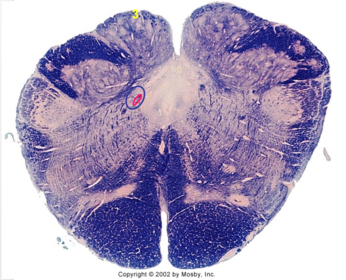

| Medullary pyramids | |

| Hypoglossal nucleus | |

| Hypoglossal nerve | |

| Dorsal motor nucleus of X | |

| Nucleus ambiguus | |

| Solitary tract | |

| Solitary nucleus | |

| ALS | |

| Medial lemniscus | |

| Medial longitudinal fasciculus | |

| Anterior spinocerebellar tract | |

| CN IX | |

| Inferior cerebellar peduncle | |

| Inferior olivary complex | |

| Dorsal cochlear nucleus | |

| Inferior vestibular nucleus | |

| Medial vestibular nucleus | |

| Spinal nucleus of V | |

| Spinal tract of V | |